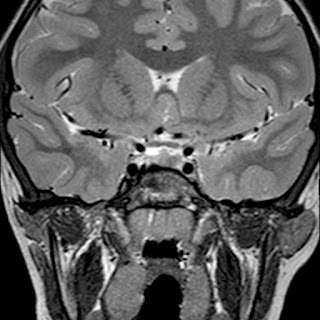

Caso neurorradiología

Paciente de 60 años con cuadro de 1 semana de evolución consistente en tropiezos frecuentes y alteración en la movilidad del miembro

inferior derecho. No refiere

cefalea u otros síntomas asociados, no pérdida de peso, no náuseas o emesis, no

sudoración nocturna. Antecedentes de hipertensión arterial y diabetes.

Resonancia magnética